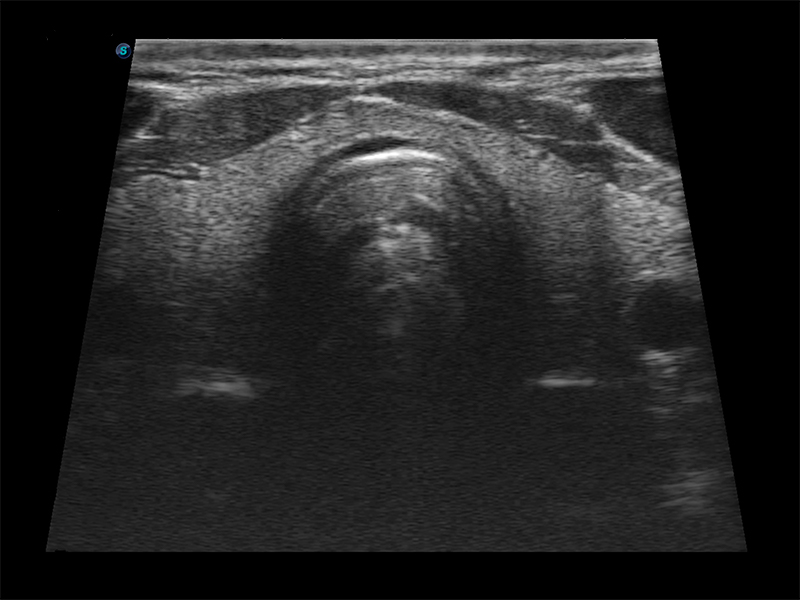

Aparat E1 to nowy model przenośnego, czarno-białego ultrasonografu, który wyposażono w bogaty pakiet funkcji wyróżniających go na tle konkurencyjnych modeli ultrasonografów klasy podstawowej. Aparat ten zapewnia użytkownikom nie tylko satysfakcjonującą jakość obrazów, lecz również usprawniony przebieg pracy.

Funkcja μ-Scan, redukcja szumu speklowego i wzmocnienie krawędzi

Obrazowanie złożone przestrzennie

Tryb PIH – obrazowanie harmoniczne z inwersją impulsu